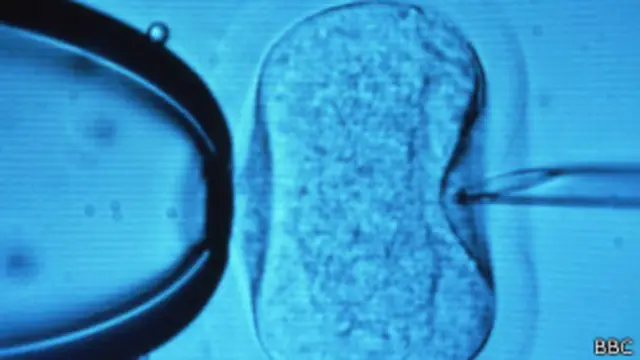

También se ha progresado con el uso moderno de imágenes de ultrasonido para recolectar óvulos con una anestesia leve, en lugar de la laparoscopia –una cirugía realizada a través de una pequeña incisión- que se practicada antiguamente.

Las técnicas desarrolladas a finales de los 80 también tuvieron un impacto importante en el tratamiento de la infertilidad masculina, con la inyección de un único espermatozoide en el óvulo.